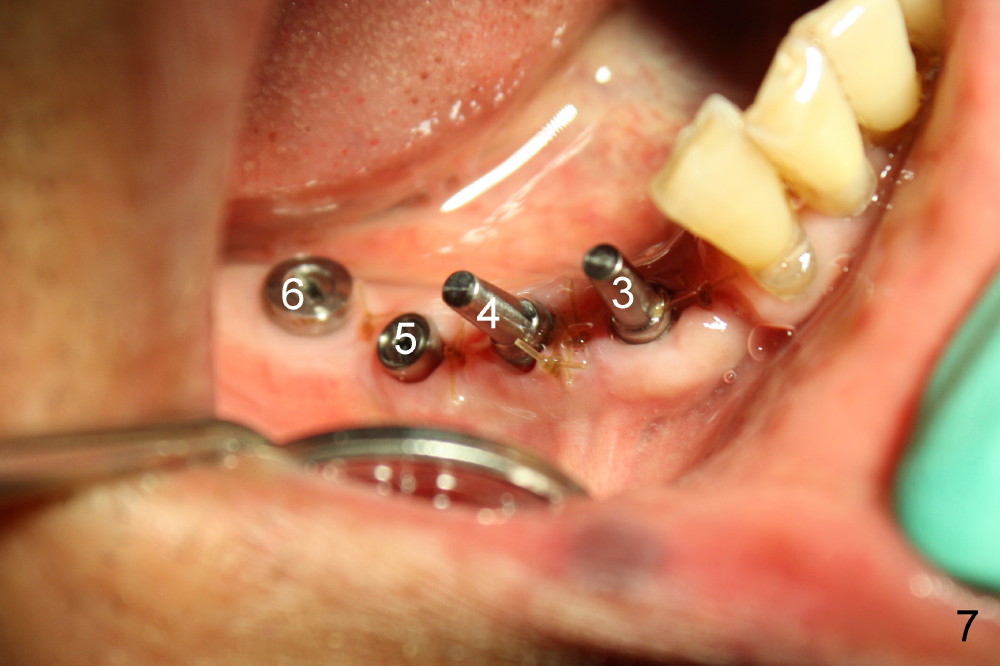

Several months ago, Philip (77 years old) was receiving chemotherapy for bladder cancer.  His lower right bridge broke down (Fig.1,2: #3-6: from canine to first molar).  The two abutment teeth (#3, 6) are nonsalvageable (Fig.4).  Ideally, immediate implant should be placed and implant-supported bridge is to be made.  The ridge at the site of #4 and 5 (premolars) is narrow.

Four months later, he returns and asks for implant restoration.  The ridge at the site of #3 is quite narrow (Fig.5).  While the socket of #3 is radiolucent (Fig.3 * under #3), there is an periapical abscess of the neighboring tooth (separate *).  It appears unsafe to place an implant at the site of #3, although anesthetic has been injected (Fig.5 *).  Instead an implant is placed at the site of #6 (5x14), further away from the infection.

Two weeks later, two of one piece implants are placed at the site of #3 and 4 (3x17), regular two piece implant at #5 (3.5x11; Fig.6).  Fig.7 is taken one week post op.